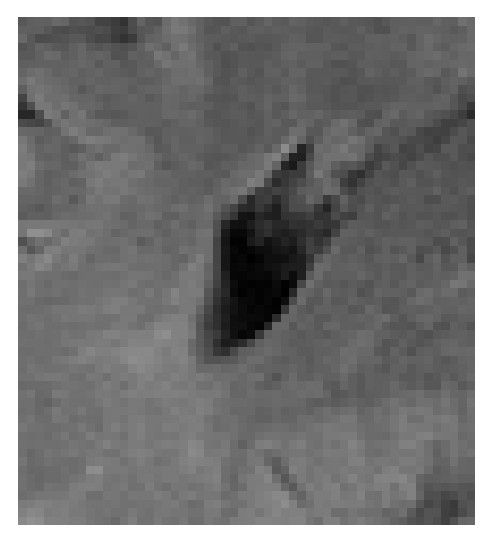

Figure 3: Reconstructions results. Rows 1 and 3: Examples of comparing the ground truth (GT) fully sampled image to the reconstructed images obtained by the three models (1-3), NPB-REC, baseline, E2E-VarNet trained with Dropout, and the NPB-REC std. map at accelerations R=4𝑅4R=4italic_R = 4, R=8𝑅8R=8italic_R = 8, respectively. Rows 2 and 4: The corresponding annotated ROIS of Nonspecific white matter lesions.

Fig. 3 presents examples of reconstruction results obtained by (1) our NPB-REC approach, (2) the baseline, and (3) Monte Carlo Dropout, for equispaced masks with two different acceleration rates R=4𝑅4R=4italic_R = 4 and R=8𝑅8R=8italic_R = 8. The reconstructed images predicted by the three models are smoother than the reference image. This is due to the fact that all the models were trained with SSIM loss, which tends to produce overly smooth reconstructions while preserving the diagnostic content and the anatomical features Sriram et al. (2020a). These images can be enhanced by dithering the image by adding a small amount of random Gaussian noise to produce a more textured reconstruction, as proposed in Sriram et al. (2020b).

Table 1 presents the mean PSNR and SSIM metrics, calculated over the whole inference set, for the three models. Our NPB-REC approach achieved significant improvements over the other methods in terms of PSNR and SSIM (Wilcoxon signed-rank test, pmuch-less-than\ll1e-4, except for SSIM values in line W, R=4𝑅4R=4italic_R = 4 where they are roughly the same for NPB-REC and Baseline). The improvement in the reconstruction performance can be noted both quantitatively from the metrics, especially for masks with acceleration rate R=8𝑅8R=8italic_R = 8, and qualitatively via the images of annotations, where our results show less smoothness than those obtained by Dropout.